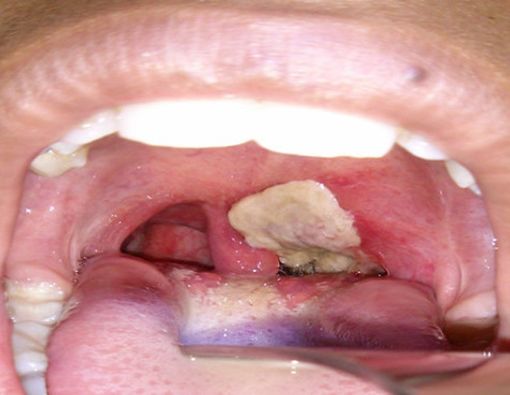

Racun yang dihasilkan bakteri penyebab difteri akan menyebabkan kematian jaringan, termasuk jaringan dalam sistem pernapasan. Akibatnya, jaringan mati tersebut akan membentuk lapisan tebal berwarna abu-abu yang dikenal dengan pseudomembran. Adanya pseudomembran menutupi saluran pernapasan, sehingga menyebabkan kesulitan bernapas.